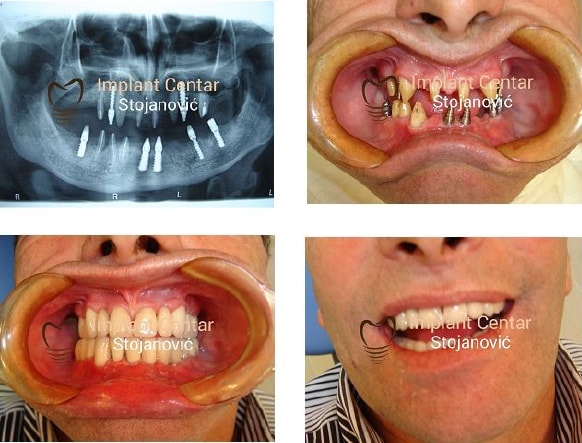

U Srbiji je mali broj implantologa koje se bave implantologijom duže od 10 godina, a još manje onih od preko 15. Mi to već radimo duže od 30 godina. Objavili smo preko 30 radova iz oblasti implantologije. Utemeljivači smo implantologije što nam uz dugogodišnje iskustvo omogućava da rešavamo najteže slučajeve, koji drugi ne mogu da reše. Za nas nema nerešivih slučajeva, polovičnih rešenja, nema kompromisa, naši pacijenti su maksimalno zaštićeni, a naša galerija predstavlja deo našeg iskustva.

U „Implant Centru Stojanović“ se rešava 98 posto najkomplikovanijih slučajeva u implatologiji, radimo bez komplikovanih dodatnih hirurških procedura (sinus lift procedura) i rešavamo sve implantološke slučajeve sa FIKSNIM PROTETSKIM RADOVIMA. Ne podržavamo i smatramo kao loše rešenje za pacijenta ALL ON 4 proceduru, jer na ovaj način štitimo pacijenta da ne nosi ponovo protezu koja je samo čvršća. Problemi koji nastaju kod ALL ON 4 procedure su mnogo češći nego kod fiksnih protetskih radova. Ove tvrdnje nisu zasnovane na podacima iz literature već na osnovu dvadesetčetvorogodišnjeg iskustva u implantologiji.

Razlikujemo se od ostalih zato što uživamo poverenje pacijenta i to poverenje težimo da očuvamo. Pacijenta štitimo iskustvom, stručnošću, i stalnim usavršavanjem u struci. Mi imamo osnova da objavimo statistike uspešnosti koja je viša od svetske, i naši radovi govore o tome. Procenu uspešnosti mogu dati samo oni koji imaju svoju statistiku na desetogodišnjem nivou, a za takvu procenu je potrebno iskustvo od najmanje 15 godina. Procena data bez takve analize je neozbiljna i neutemeljena na realnim osnovama.